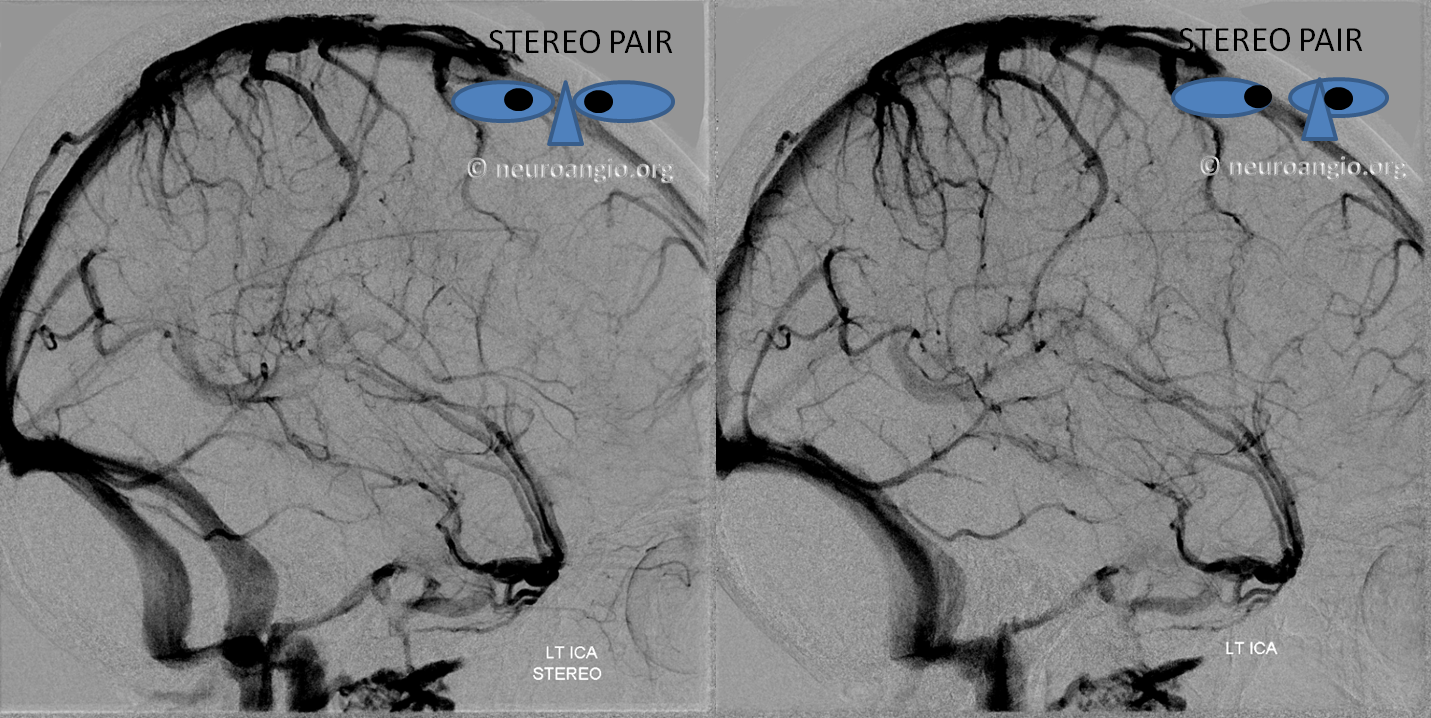

Stereo of the same

Another example in Anaglyph Stereo